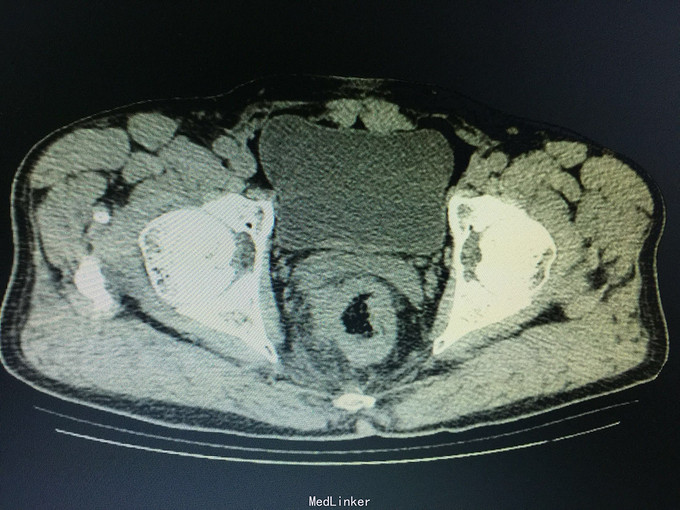

一般状态好,无贫血貌,肛门外缘不规整,肛门指诊:距肛缘4cm可及溃疡性肿物,近环形,固定,指套染陈旧血。 辅助检查:盆腔CT:直肠管壁不规则肥厚,官腔偏心性狭窄,周围见条索影及结节影。

诊断:直肠癌, 预约结肠镜检查:距肛缘4cm见环肠肿物,凸凹不平,表面覆污秽苔,质硬,界不清。 病理结果为直肠腺癌。 病人回当地医院接受治疗。